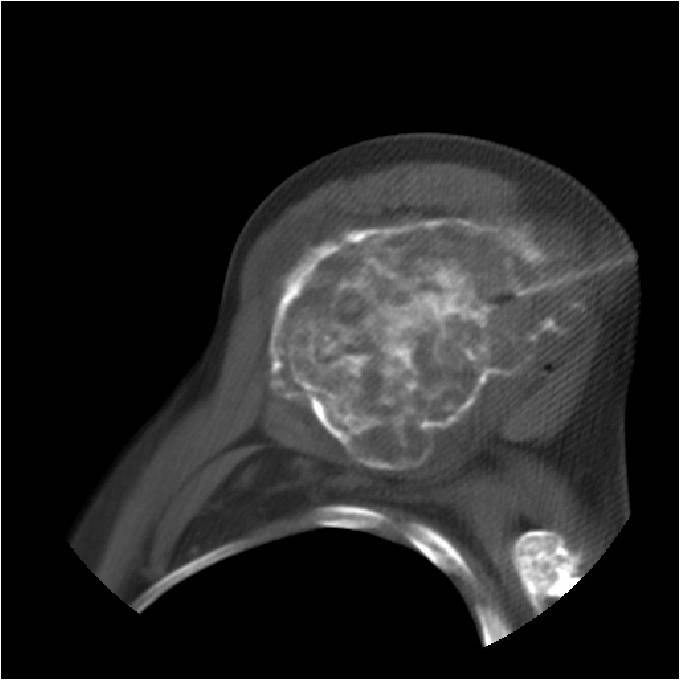

- Localized, radiolucent defect usually with punctate calcifications

- Calcifications are stippled, punctate, popcorn like calcifications and “Ring and Arc” calcifications

- Cartilage tumors grow in a lobular manner. The perimeters of the lobules undergo

- enchondral ossification that may calcify. If the entire perimeter of the lobule calcifies it appears

- radiographically as a “Ring”. If a portion of the perimeter of a lobule calcifies it forms an “Arc” on

- an X-ray.

- Chondroid matrix with calcifications in majority of tumors

- Lobulated margin (Lobular Growth Pattern)

- T1 Weighted Images: Intermediate Signal Intensity

- Calcifications will be low signal

- T2 Weighted Images: High Signal Intensity

- High water content shows as high signal on T2 weighted images

Metaphyseal Tumor Heavy Calcifications Ring and Arc Pattern of Calcifications Minimal Endosteal Scalloping No Cortical Destruction No Periosteal Reaction No Cortical Destruction No Soft Tissue Component